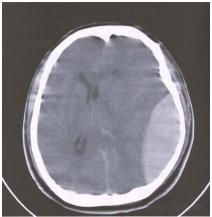

51 一位 38 歲男性,於高速公路發生撞車意外,送達急診室時的理學檢查報告如下:血壓 140/95 mmHg, 心跳 90/分,GCS 昏迷指數 8 分(E1M5V2),左側瞳孔放大(左:6 mm,右:3 mm 直徑),右側 肢體偏癱。其緊急電腦斷層掃描如下圖,則這位病患最有可能的臨床診斷是:

(A)急性左側硬腦膜下出血(subdural hematoma) (B)急性左側硬腦膜上出血(epidural hematoma) (C)急性左側腦內出血(intracerebral hematoma) (D)慢性左側硬腦膜下出血